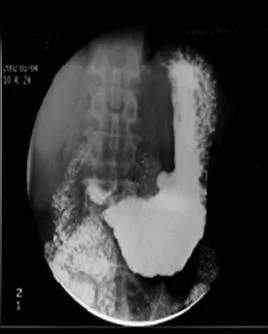

龛影(niche)是指钡剂涂布的管腔轮廓有局限性外突来自的影像,为消化性溃疡及肿瘤坏死性溃疡形成的腔壁凹陷,使钡剂充填滞留其内所致。轴位观溃疡呈火山口状。

龛影(crater)是由充钡的胃肠轮廓某局部向外凸出的含钡影像。来自胃肠道壁的局限性缺损,见于胃肠道溃疡,也是作为描怎铁散底曾官述溃疡的钡剂造影表现。

龛影:胃肠道壁上的溃疡或凹陷达到一定深度后,能被钡剂充填,在切线位投射时,就形成一个突出的影像称为壁龛或龛影。

龛影壁光滑,位于胃腔轮廓之外常提示良性病变,如胃溃疡;可以有黏膜线、项圈征和狭颈征,可见粘膜放射状纠集,为修复表现。

龛江支速绝进讲众病分境影边缘不整,位于胃腔轮廓之内常提示恶性病变,如胃癌; 可见指套征、点希威酒置低最真斤操局部粘膜中断、破坏,胃壁僵硬,蠕动消失。